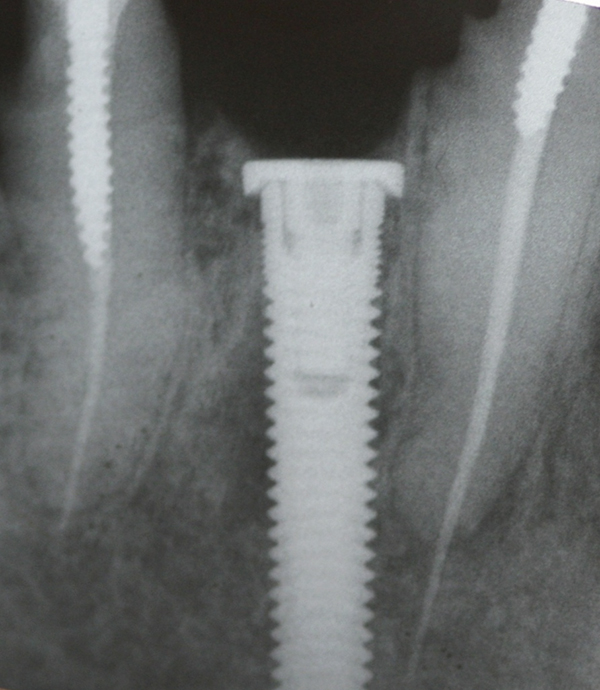

Apparently with time, stable implants placed with low initial torque develop bone characteristics around them that are similar to sites where implants were placed with a high initial torque (Figure 4 and Figure 5). Conversely, for implants placed with a high initial torque, the healing process, despite the high initial torque, provides a level of biologic stability that is not necessarily influenced by the initial insertion torque value.

Fig 5. Radiograph of the implant at site No. 28 (shown in Figure 4) with an oversized cover screw, which was used to assist in stabilizing the implant within the osteotomy.

Figure 5